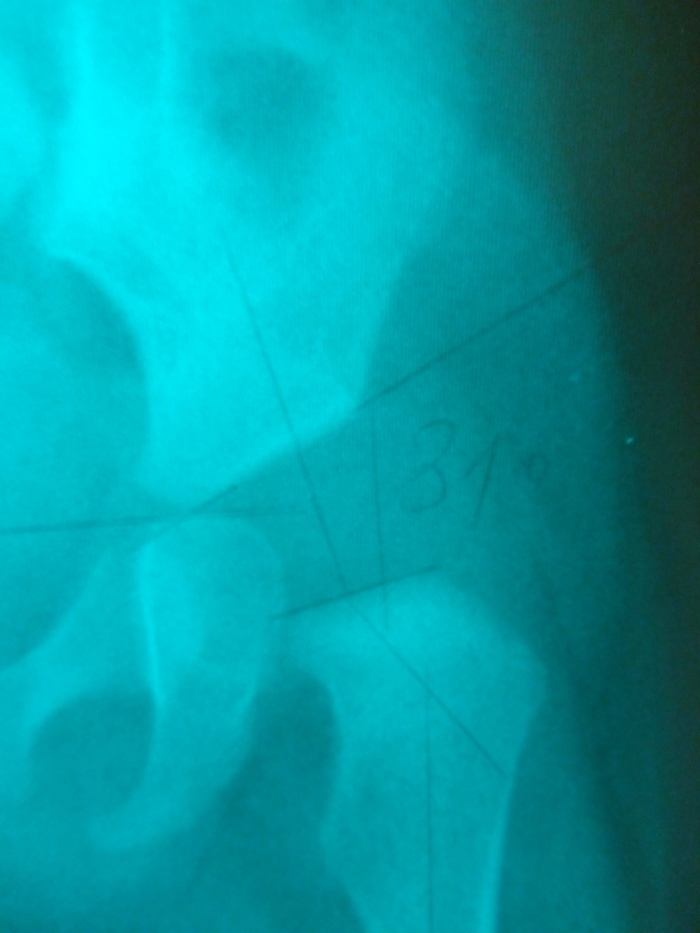

Вопрос врачам. Отсутствие ядер тазобедренных

Добрый день! Прошу, помогите! Носим шину Орлет (без шарниров), но дочь никак не может к ней привыкнуть. И дело не только в разведении ножек, а в том что очень не удобно спину, возможно даже больно. Плохо спит, постоянно плачет. Ей 7 месяцев, но ещё не сидит и не ползает, т.к. гипотонус, слабые мышцы. Мы делаем всё что прописал врач: физио, ЛФК, массаж, но я боюсь, что за 4 месяца в шине мышцы совсем станут слабыми, ведь она полностью ограничивает движения. Скажите, пожалуйста, сколько времени нам можно находится без шины чтобы заниматься физкультурой? Можно ли спать без шины? Может сменить шину? Можно ли сидеть ребенку (я совсем запуталась, врачи говорят по разному)? И какой вы, с точки зрения своего опыта, дадите нам прогноз? Пожалуйста, очень интересно ваше мнение. Спасибо.